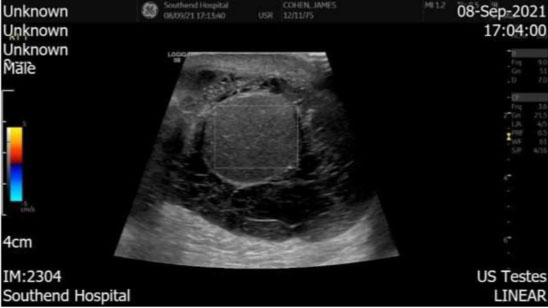

The Doppler ultrasound scan performed 2 weeks after the initial review described the right testicle as appearing diffusely hypoechoic with no presence of internal vasculature. The right scrotum also had a collection with internal septum suggestive of an infected hematoma (Figure 1). The left testis and epididymis had normal echotexture and vasculature. The ultrasound scan therefore showed radiological features of an avascular right sided testicle (Figure 2).

Figure 1: Ultrasound scan of the right testicle showing internal septum suggestive of an infected hematoma.

Figure 2: Doppler ultrasound scan of the right testicle showing no internal vasculature.

However, when diagnosing scrotal pathologies especially after a surgery, physical examination, although important, is not completely reliable. The most effective way of ruling out other scrotal and testicular differential diagnoses would be with an ultrasound scan [5]. As in this case, the scan confirmed an infected scrotal hematoma but also showed an avascular testicle.